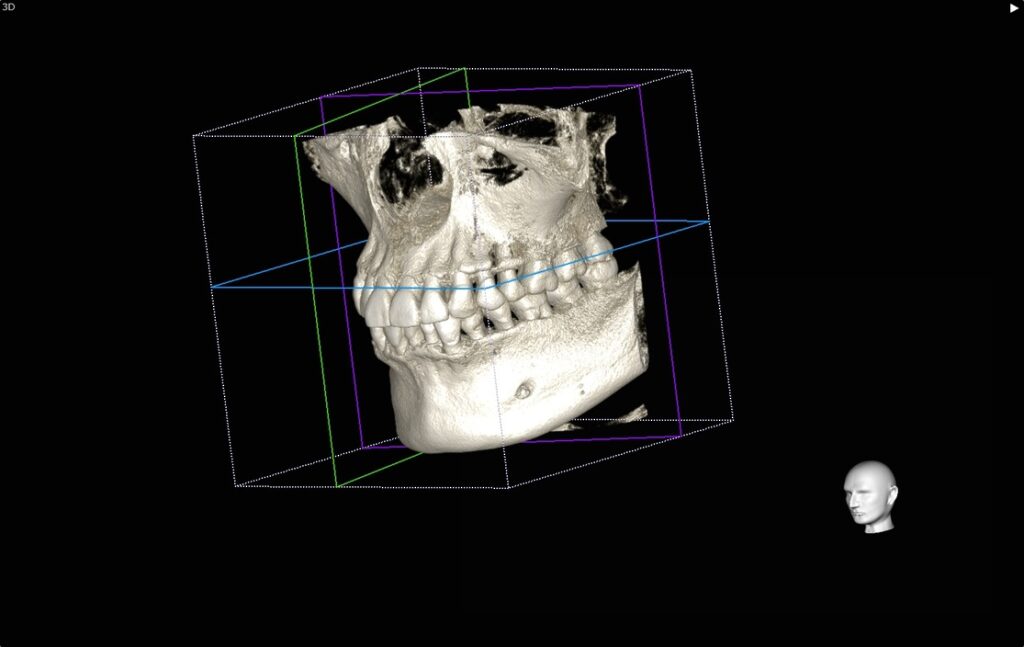

CT撮影を行うと、歯、骨が立体で描かれます。

また同時に、1本1本の歯をいろんな方向から見ることができます。

今回の右上の歯でいうと、

オレンジでマークしたところが黒く染まっているのがお分かりいただけるかと思います。

本来は白色〜鼠色で描かれ、骨があるべき部位です。

患者さんにも一目でお分かりいただけます、状態がわかれば、治療もスムーズに進みます。